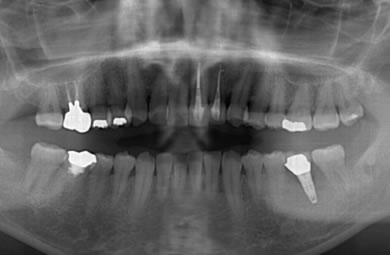

インプラントの症例写真 IMPLANT

インプラント治療+セラミック治療

| 治療方針 | 前歯部の審美的回復をセラミック治療で行う。臼歯部の審美的・機能的回復をインプラント治療で行う。 | ||||||||||||||||||||||||||||||||

| 治療内容 | インプラント1本、メタルボンドセラミック1本、オールセラミック2本(オールセラミック用の土台2本) | ||||||||||||||||||||||||||||||||

| 総治療費 | 608,667円 | ||||||||||||||||||||||||||||||||

| 治療期間 | 4ヶ月 |